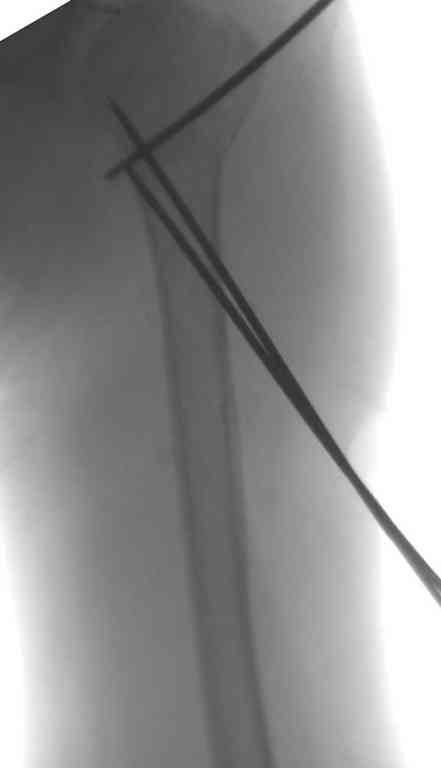

Неправильно выбранная тактика по фиксации или технические ошибки во время операции могут привести к серьезным осложнениям. Здесь привожу

пример из нашей практики, вроде обычный перелом шейки, фиксированный популярным методом "Сиэтла" - множественными спицами 2.8 мм с резьбой на конце.

При первичном осмотре в поликлинике через 3 недели обнаружили миграцию двух спиц, срочно госпитализированному на второй день перед операцией на всякий случай сделали снимок, одна спица находилась под ключицей в шейном отделе (на снимке).